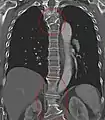

Sacralization of the L5 vertebra is seen at the lower right of the image.

Sacralization of the fifth lumbar vertebra (or sacralization) is a congenital anomaly, in which the transverse process of the last lumbar vertebra (L5) fuses to the sacrum on one side or both, or to ilium, or both. These anomalies are observed in about 3.5 percent of people, and it is usually bilateral but can be unilateral or incomplete (ipsilateral or contralateral rudimentary facets) as well. Although sacralization may be a cause of low back pain, it is asymptomatic in many cases (especially bilateral type). Low back pain in these cases most likely occurs due to biomechanics. In sacralization, the L5-S1 intervertebral disc may be thin and narrow. This abnormality is found by X-ray.